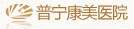

△阻生智牙。

低位埋伏阻生智齒是臨床上常見的口腔疾病,易導緻颌骨囊腫、骨髓炎和冠周炎等,影響患者的正常生活。對這種沒有咀嚼功能,且反複引發口腔問題的智牙是需要拔除的。但此類智牙的位置較深,骨阻力較大,周圍結構複雜,操作空間有限,要拔除是非常有挑戰性的。